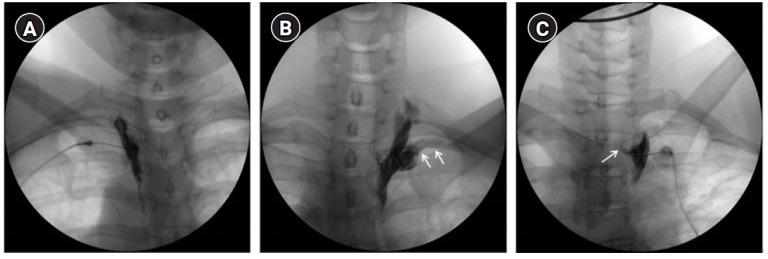

Twenty-two patients who were suffering from complex regional pain syndrome or lymphedema after breast cancer surgery were managed with two or three times of thoracic SBs. Therefore, injections of 63 thoracic SBs from 22 patients were enrolled in this study. An investigator who did not attend the procedure evaluated the occurrence of intercostal or epidural spread using anteroposterior fluoroscopic images.

The overall incidence of inadvertent intercostal or epidural spread of contrast was 47.5%. Among the inadvertent injections, intercostal spread (34.9%) was more frequent than epidural spread (12.6%). Only 52.5% of the thoracic SBs demonstrated successful contrast spread without any inadvertent spread. The mean difference in skin temperature between the blocked and unblocked sides was 2.5 ± 1.8ºC. Fifty-nine (93.6%) injections demonstrated more than 1.5ºC difference.

22例患有复杂性区域疼痛综合征或乳腺癌手术后淋巴水肿的患者接受了两到三次胸段SBs治疗。因此,本研究纳入了22例患者的63次胸段SBs注射。一名未参与该操作的研究者使用前后位透视图像评估肋间或硬膜外扩散的发生情况。

造影剂意外肋间或硬膜外扩散的总体发生率为47.5%。在意外注射中,肋间扩散(34.9%)比硬膜外扩散(12.6%)更频繁。只有52.5%的胸段SBs显示造影剂成功扩散且无任何意外扩散。阻滞侧与未阻滞侧皮肤温度的平均差异为2.5±1.8℃。59次(93.6%)注射显示差异超过1.5℃。